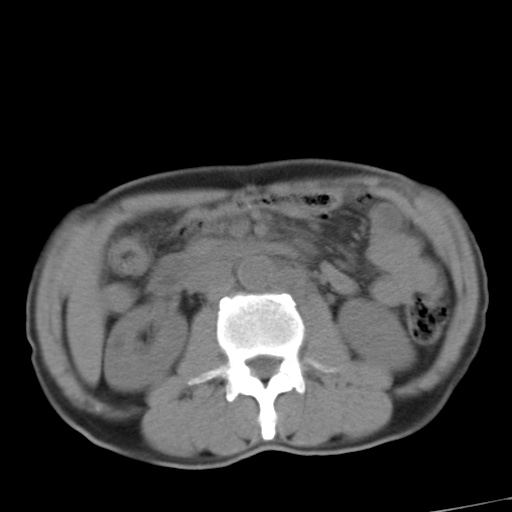

标题: CT17975:请求会诊。男、57岁。上腹部胀痛2天。临床诊断:糜 [打印本页]

标题: CT17975:请求会诊。男、57岁。上腹部胀痛2天。临床诊断:糜

肝脏多发类圆形低密度影,考虑肝脏转移瘤,肝胃韧带一淋巴结肿大,原发?胃癌?

考虑胃癌并肝脏及腹膜后淋巴结转移;不排除淋巴瘤。

肝内转移瘤,腹腔及腹膜后淋巴结转移。